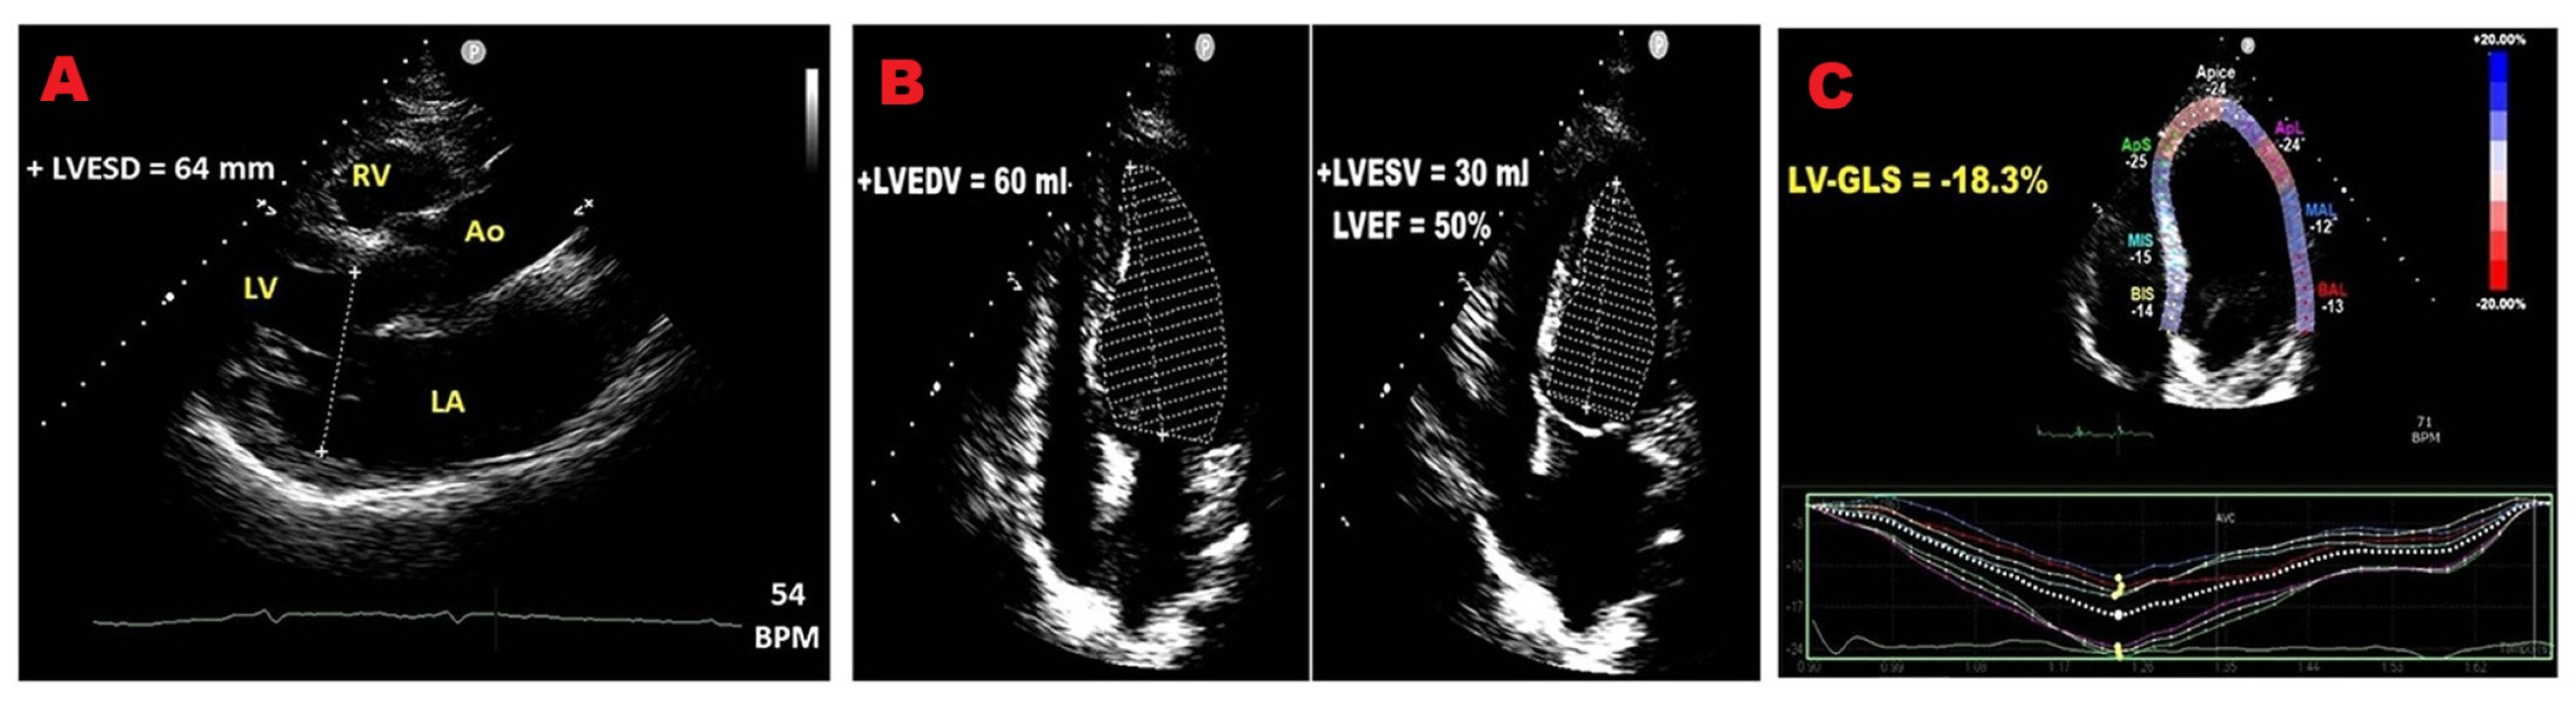

3.3. Left Ventricular Function

3.4. Left Ventricular Global Longitudinal Strain